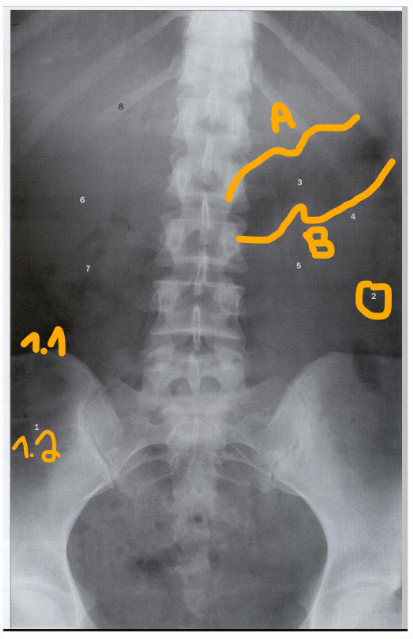

1.1: colon ascendens

1.2: caecum

2: colon descendens

A: curvatura minor

B: curvatura major